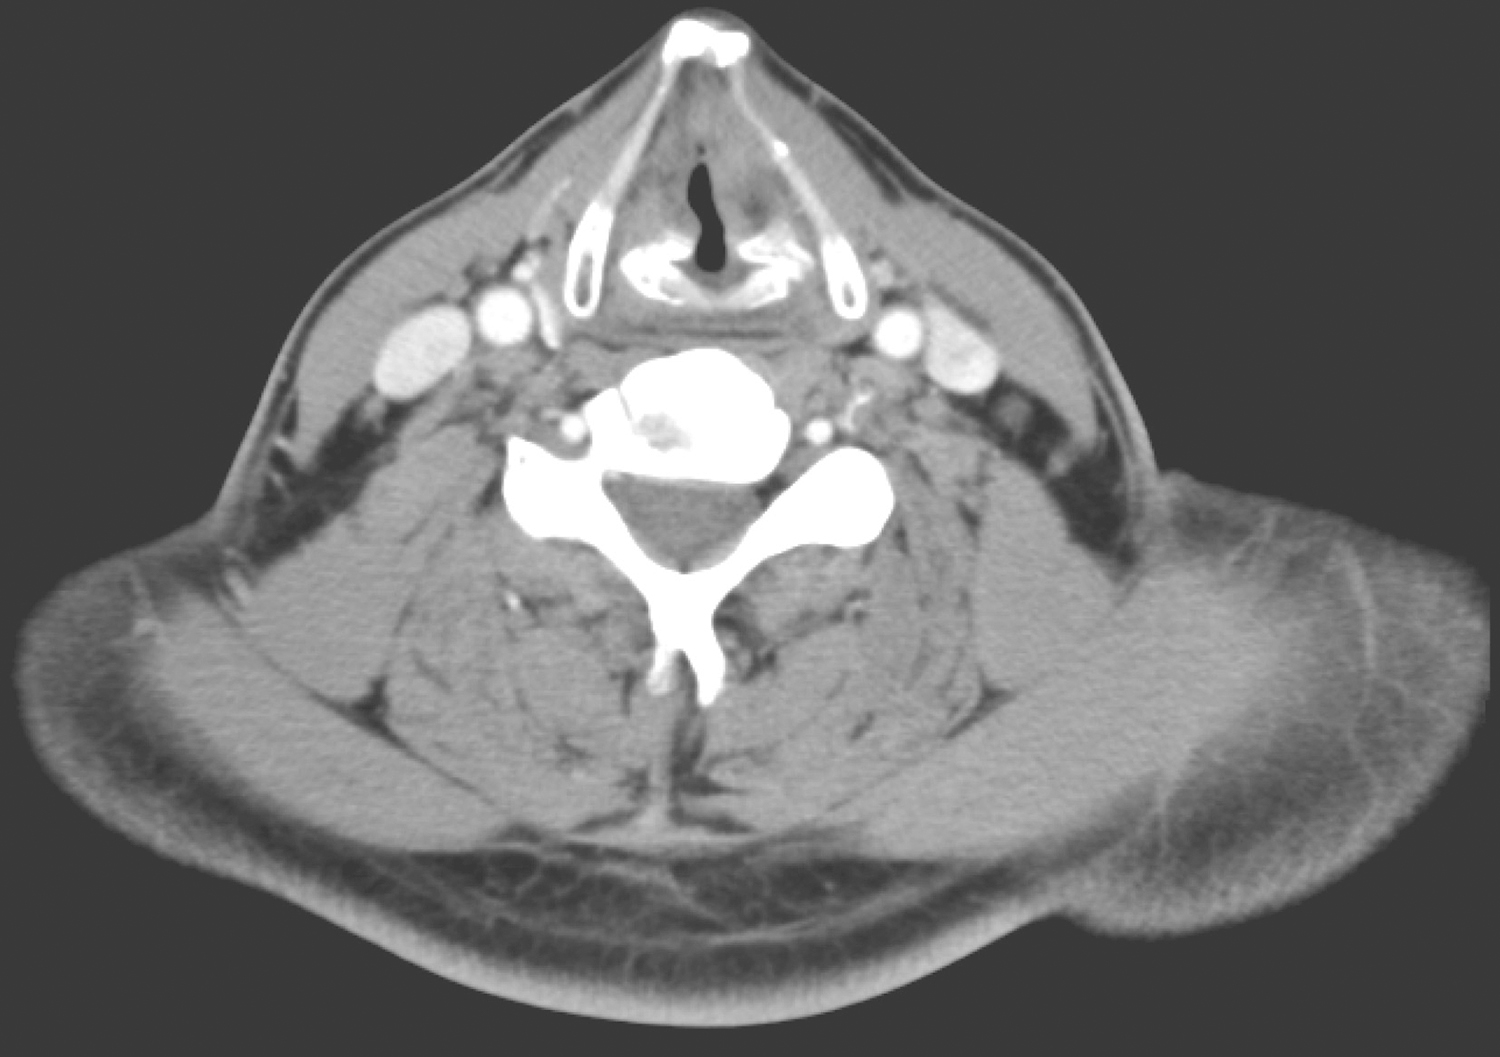

1小时条评论31岁女性,查体发现癌胚抗原升高2年,发现甲状腺肿物2个月余,临床符合甲状腺髓样癌,如何治疗? 【病例简介】 患者女性,31岁。因查体发现癌胚抗原升高2年,发现甲状腺肿物2个月余,于2018年3月5日收入本院头颈外科。2年前查体发现癌胚抗原升高,数值逐渐增...